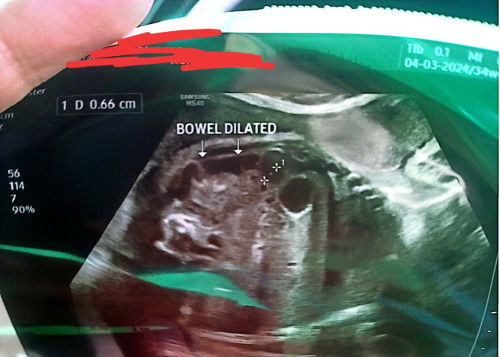

Usus baby bengkak

Hai semua. Tadi saya saja pergi scan. Skrg dah 34w+ . Alhamdulillah berat , air ketumban semua okay. Tapi sono cakap usus baby bengkak sikit. Saya tanya bahaya ke? Dia cakap kadang masa lahir dia akan normal balik tapi dia suruh bagitahu je kat KK nanti. Masa detail scan okay je semua. Sono cakap kadang masa hujung2 mengandung baru nampak. Saya pun lupa nak tanya punca kenapa. Mommy2 ada pengalaman tak?